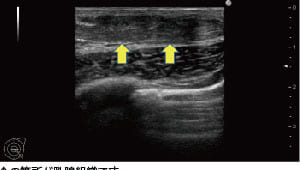

真性女性化乳房とは?